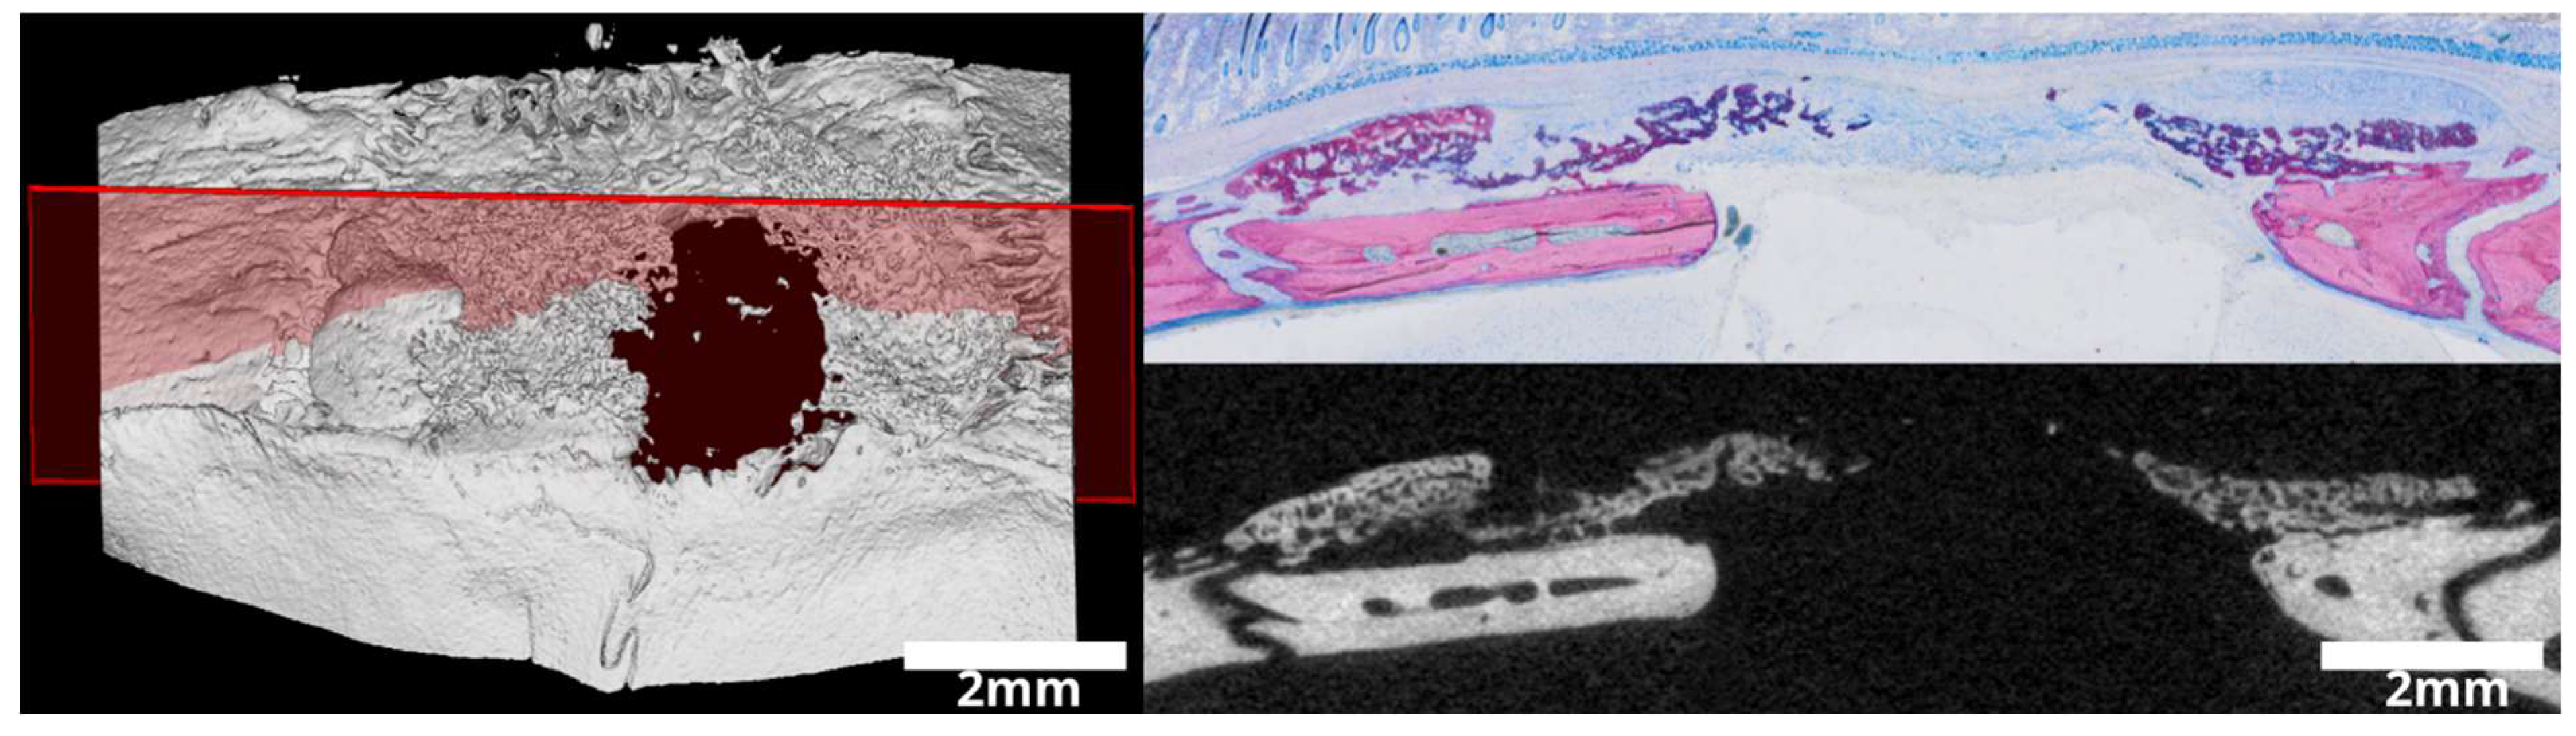

3.1. Intact and Minced Collagen Membranes: µCT Analysis

3.2. Intact Collagen Membranes: Histological Analysis

3.3. Minced Collagen Membranes: Histological Analysis